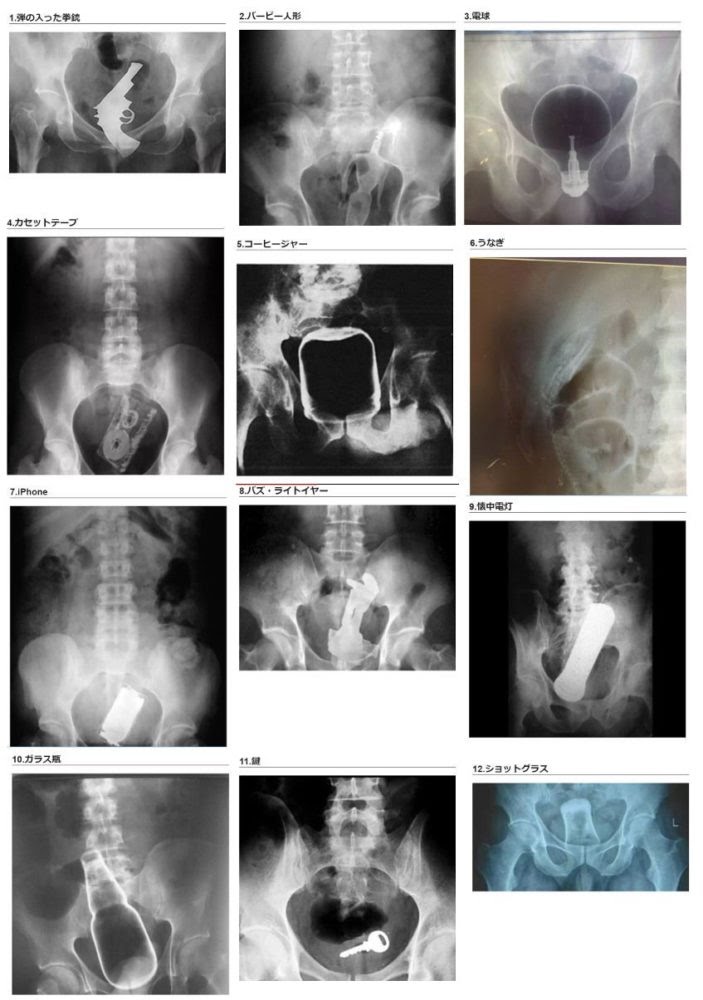

• 77122/04/18(月) 13:45:31

論文欲張りセット

• 78二次元好きの匿名さん22/04/18(月) 13:46:19

>>77

ホラー画像定期

• 79二次元好きの匿名さん22/04/18(月) 13:46:31

どうして

• 80二次元好きの匿名さん22/04/18(月) 13:46:51

>>63

シ、シャンプーがかかってて…

• 81二次元好きの匿名さん22/04/18(月) 13:47:07

コラだと言ってくれ

人体にそんなのを入れた人がいるなんて信じたくない……

• 82二次元好きの匿名さん22/04/18(月) 13:47:15

電球を優しく包み込む骨盤でくそ笑った

• 83二次元好きの匿名さん22/04/18(月) 13:47:40

サイズを見てると鍵が一番小さくてマシに見えてしまう

いや異物挿入はどれもやばいんだけどさ

• 84二次元好きの匿名さん22/04/18(月) 13:47:49